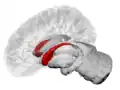

![]() Caudate nucleus (in red) shown within the brain | |

The caudate nuclei are located near the center of the brain, sitting astride the thalamus. There is a caudate nucleus within each hemisphere of the brain. Individually, they resemble a C-shape structure with a wider "head" (caput in Latin) at the front, tapering to a "body" (corpus) and a "tail" (cauda). Sometimes a part of the caudate nucleus is referred to as the "knee" (genu).[7] The caudate head receives its blood supply from the lenticulostriate artery while the tail of the caudate receives its blood supply from the anterior choroidal artery.[8]

The head and body of the caudate nucleus form part of the floor of the anterior horn of the lateral ventricle. After the body travels briefly towards the back of the head, the tail curves back toward the anterior, forming the roof of the inferior horn of the lateral ventricle. This means that a coronal (on a plane parallel to the face) section that cuts through the tail will also cross the body and head of the caudate nucleus.